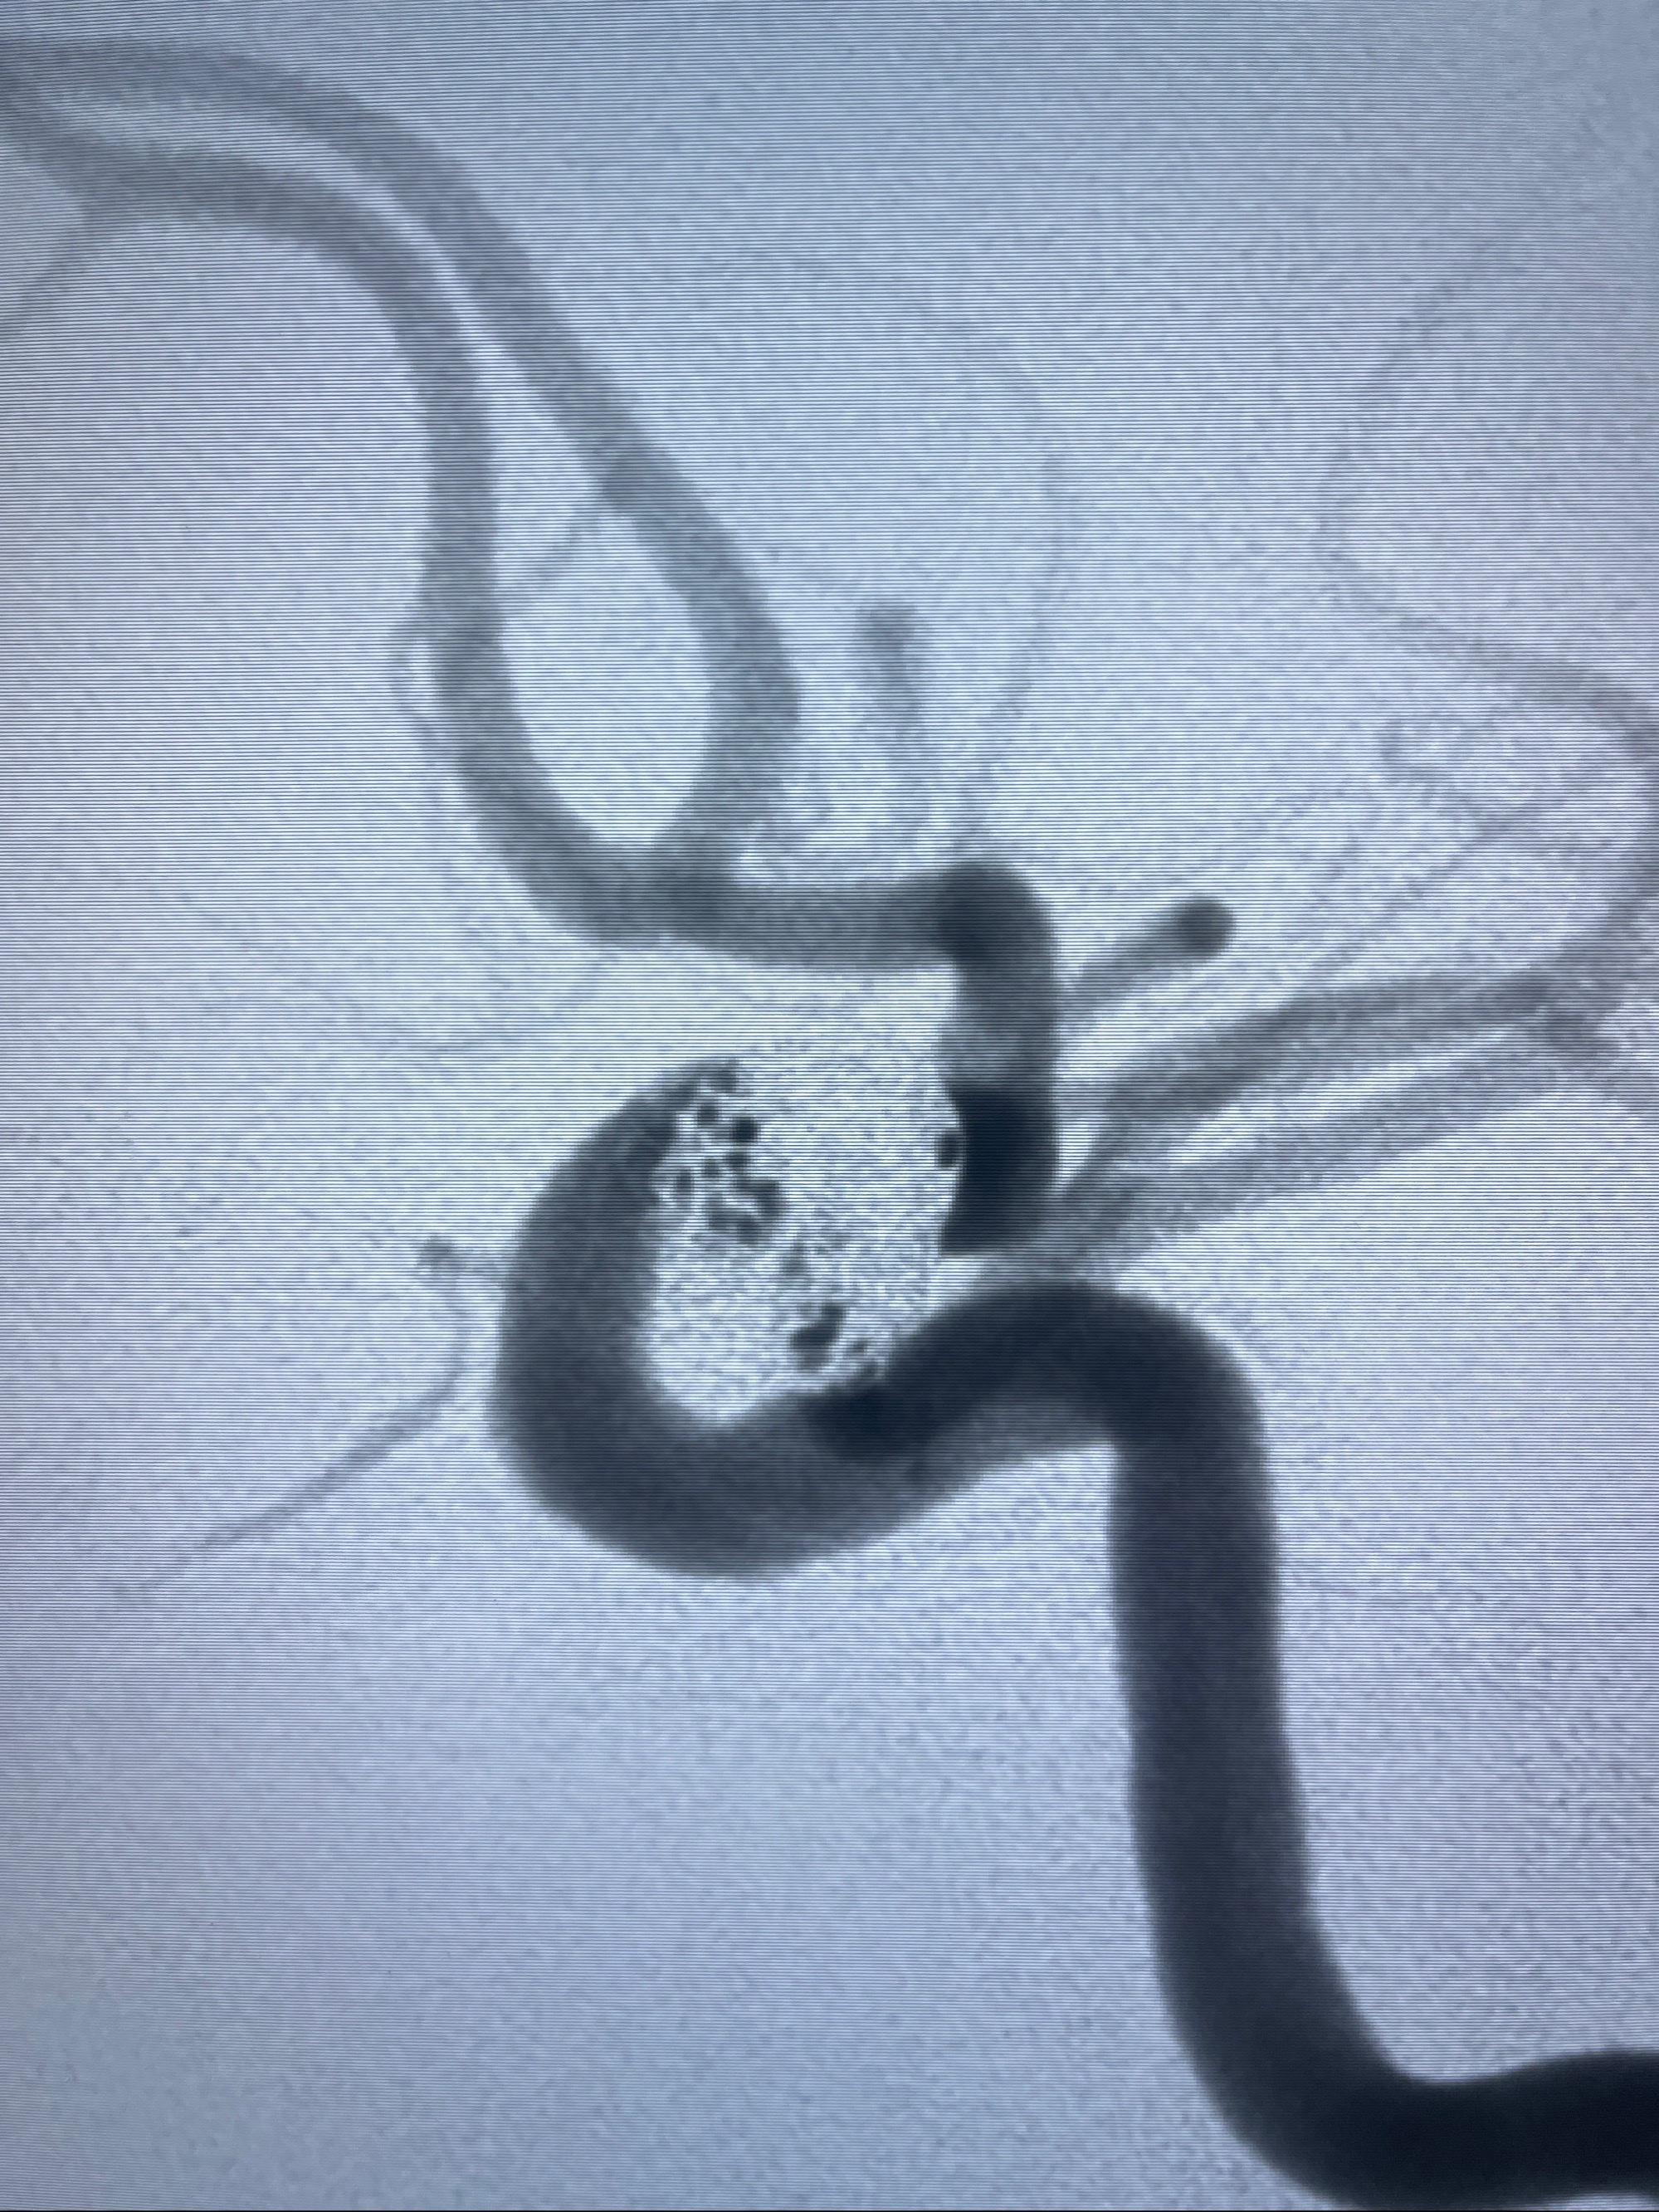

2023-08-30DSA:左侧颈内动脉眼动脉动脉瘤,约3*9.2*7.3mm大小

密网支架辅助栓塞

- Tubridge 4.0-20mm密网支架

- 加奇微弹簧圈:7*30/6*20/5*20/2*8

术后3D显示支架贴壁佳